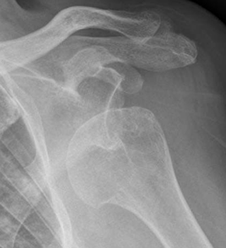

Se diagnostica cuando la cabeza humeral, se localiza por debajo de la apófisis coracoides. (11). (Fig 45 A y B, 46 y 47).

Fig 45 A. Luxación anterior.

Rx AP. Cabeza humeral por debajo de la coracoides, por luxación anterior.